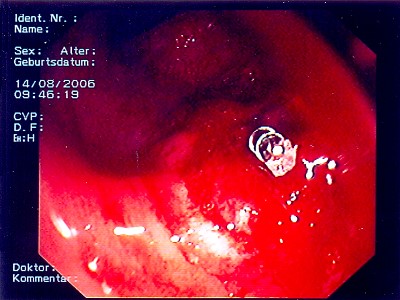

Gut sichtbarer Blutstrahl nach Abtragung eines Polypen

Sichere Blutstillung durch einen Metallclip